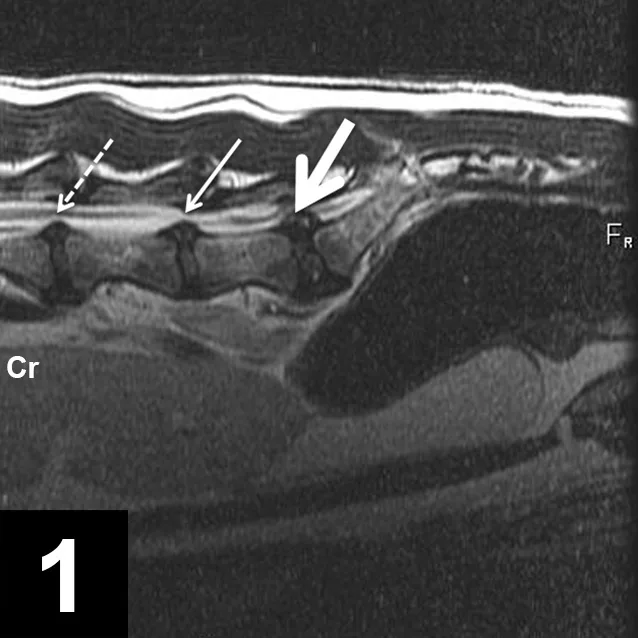

• Complete spinal MRI revealed multifocal intervertebral disc degeneration throughout the mid-thoracic, caudal thoracic, and lumbar vertebral column, with intervertebral disc herniation resulting in mild spinal cord compression at T13–L1, L1–L2, L2–L3, L5–L6, and L6–L7 (Figure 1). The L7–S1 intervertebral disc was also herniated, leading to severe bilateral nerve root compression at this location (Figure 2). The discs in the cervical and cranial thoracic spine were adequately hydrated.

Figure 1

Sagittal T2 weighted image of the caudal lumbar spine and sacrum. The L5–L6 (dashed white arrow), L6–L7 (thin white arrow), and L7–S1 (thick white arrow) intervertebral discs are protruded, which is consistent with intervertebral disc herniation.